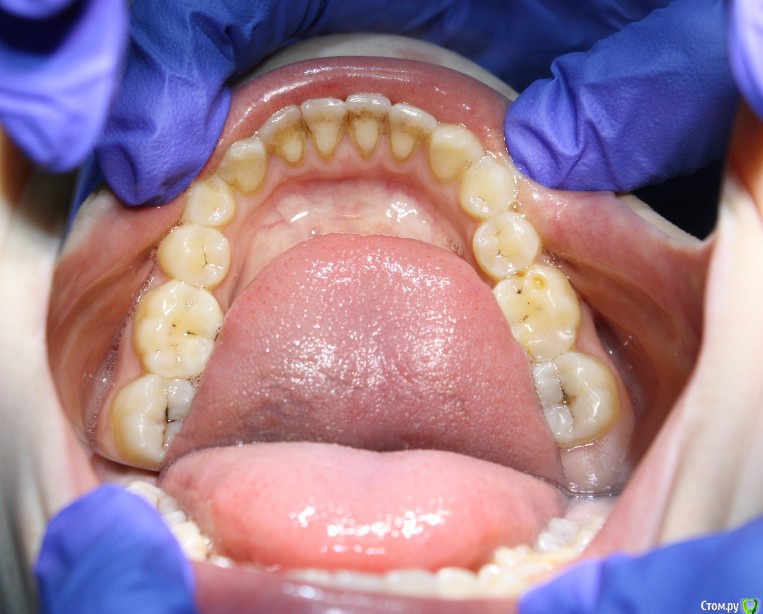

Здравствуйте коллеги! На консультацию обратилась пациентка, сейчас находится на ортодонтическом лечении. Предистория: три года назад обратилась к стоматологам с жалобой на неудовлетворительную эстетику фронтального отдела, вследствие врожденного отсутствия латеральных резцов. Ей было предложено ортодонтически создать место для боковых резцов, затем провести имплантацию и протезирование на имплантатах 12, 22.

Затем, с ее слов, идет длительный этап ортодонтии, почти 3 года, вследствие которого получили немного места для двоек, которого не достаточно для иплантации, так же центральные резцы ушли вперед, образовалась саггитальная щель.

Фото сегодня:post-461-0-94195200-1456407270_thumb.jpgpost-461-0-97652100-1456407271_thumb.jpgpost-461-0-40898500-1456407273_thumb.jpgpost-461-0-68973300-1456407274_thumb.jpgpost-461-0-88108800-1456407275_thumb.jpgpost-461-0-99061300-1456407276_thumb.jpgpost-461-0-92547500-1456407277_thumb.jpgpost-461-0-02811200-1456407279_thumb.jpgpost-461-0-05035300-1456407280_thumb.jpgpost-461-0-27197600-1456407281_thumb.jpg